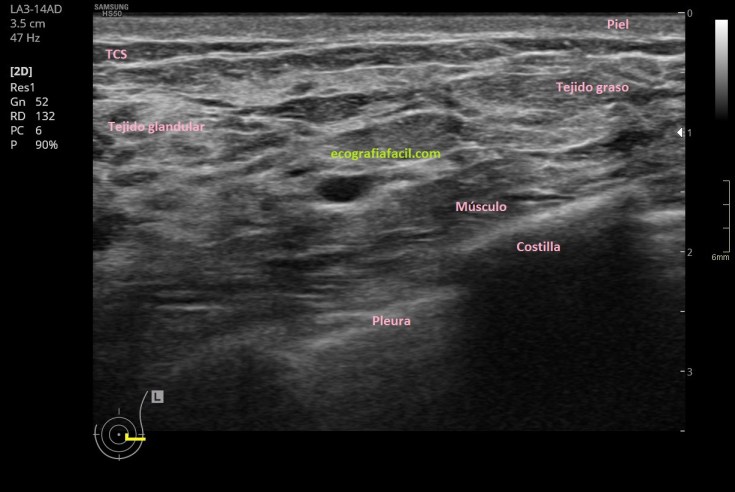

En el caso que te presento hoy es una masa de semiología isoecogénica, heterogénea, de gran tamaño, ovoidea, que ocupa la región periareolar cerca de la línea intercuadrántica externa de la mama izquierda, mama que como puedes ver en la imagen 1 es una mama de alta densidad lo que siempre dificulta la sensibilidad de la técnica.

En la imagen 1 tienes un repaso de la ecoarquitectura normal de una mama, siempre, a expensas de la variable cantidad de tejido glandular y tejido graso que conjugue dicha glándula y que nos hablará si es una mama de predominio graso, mixto o una mama densa.